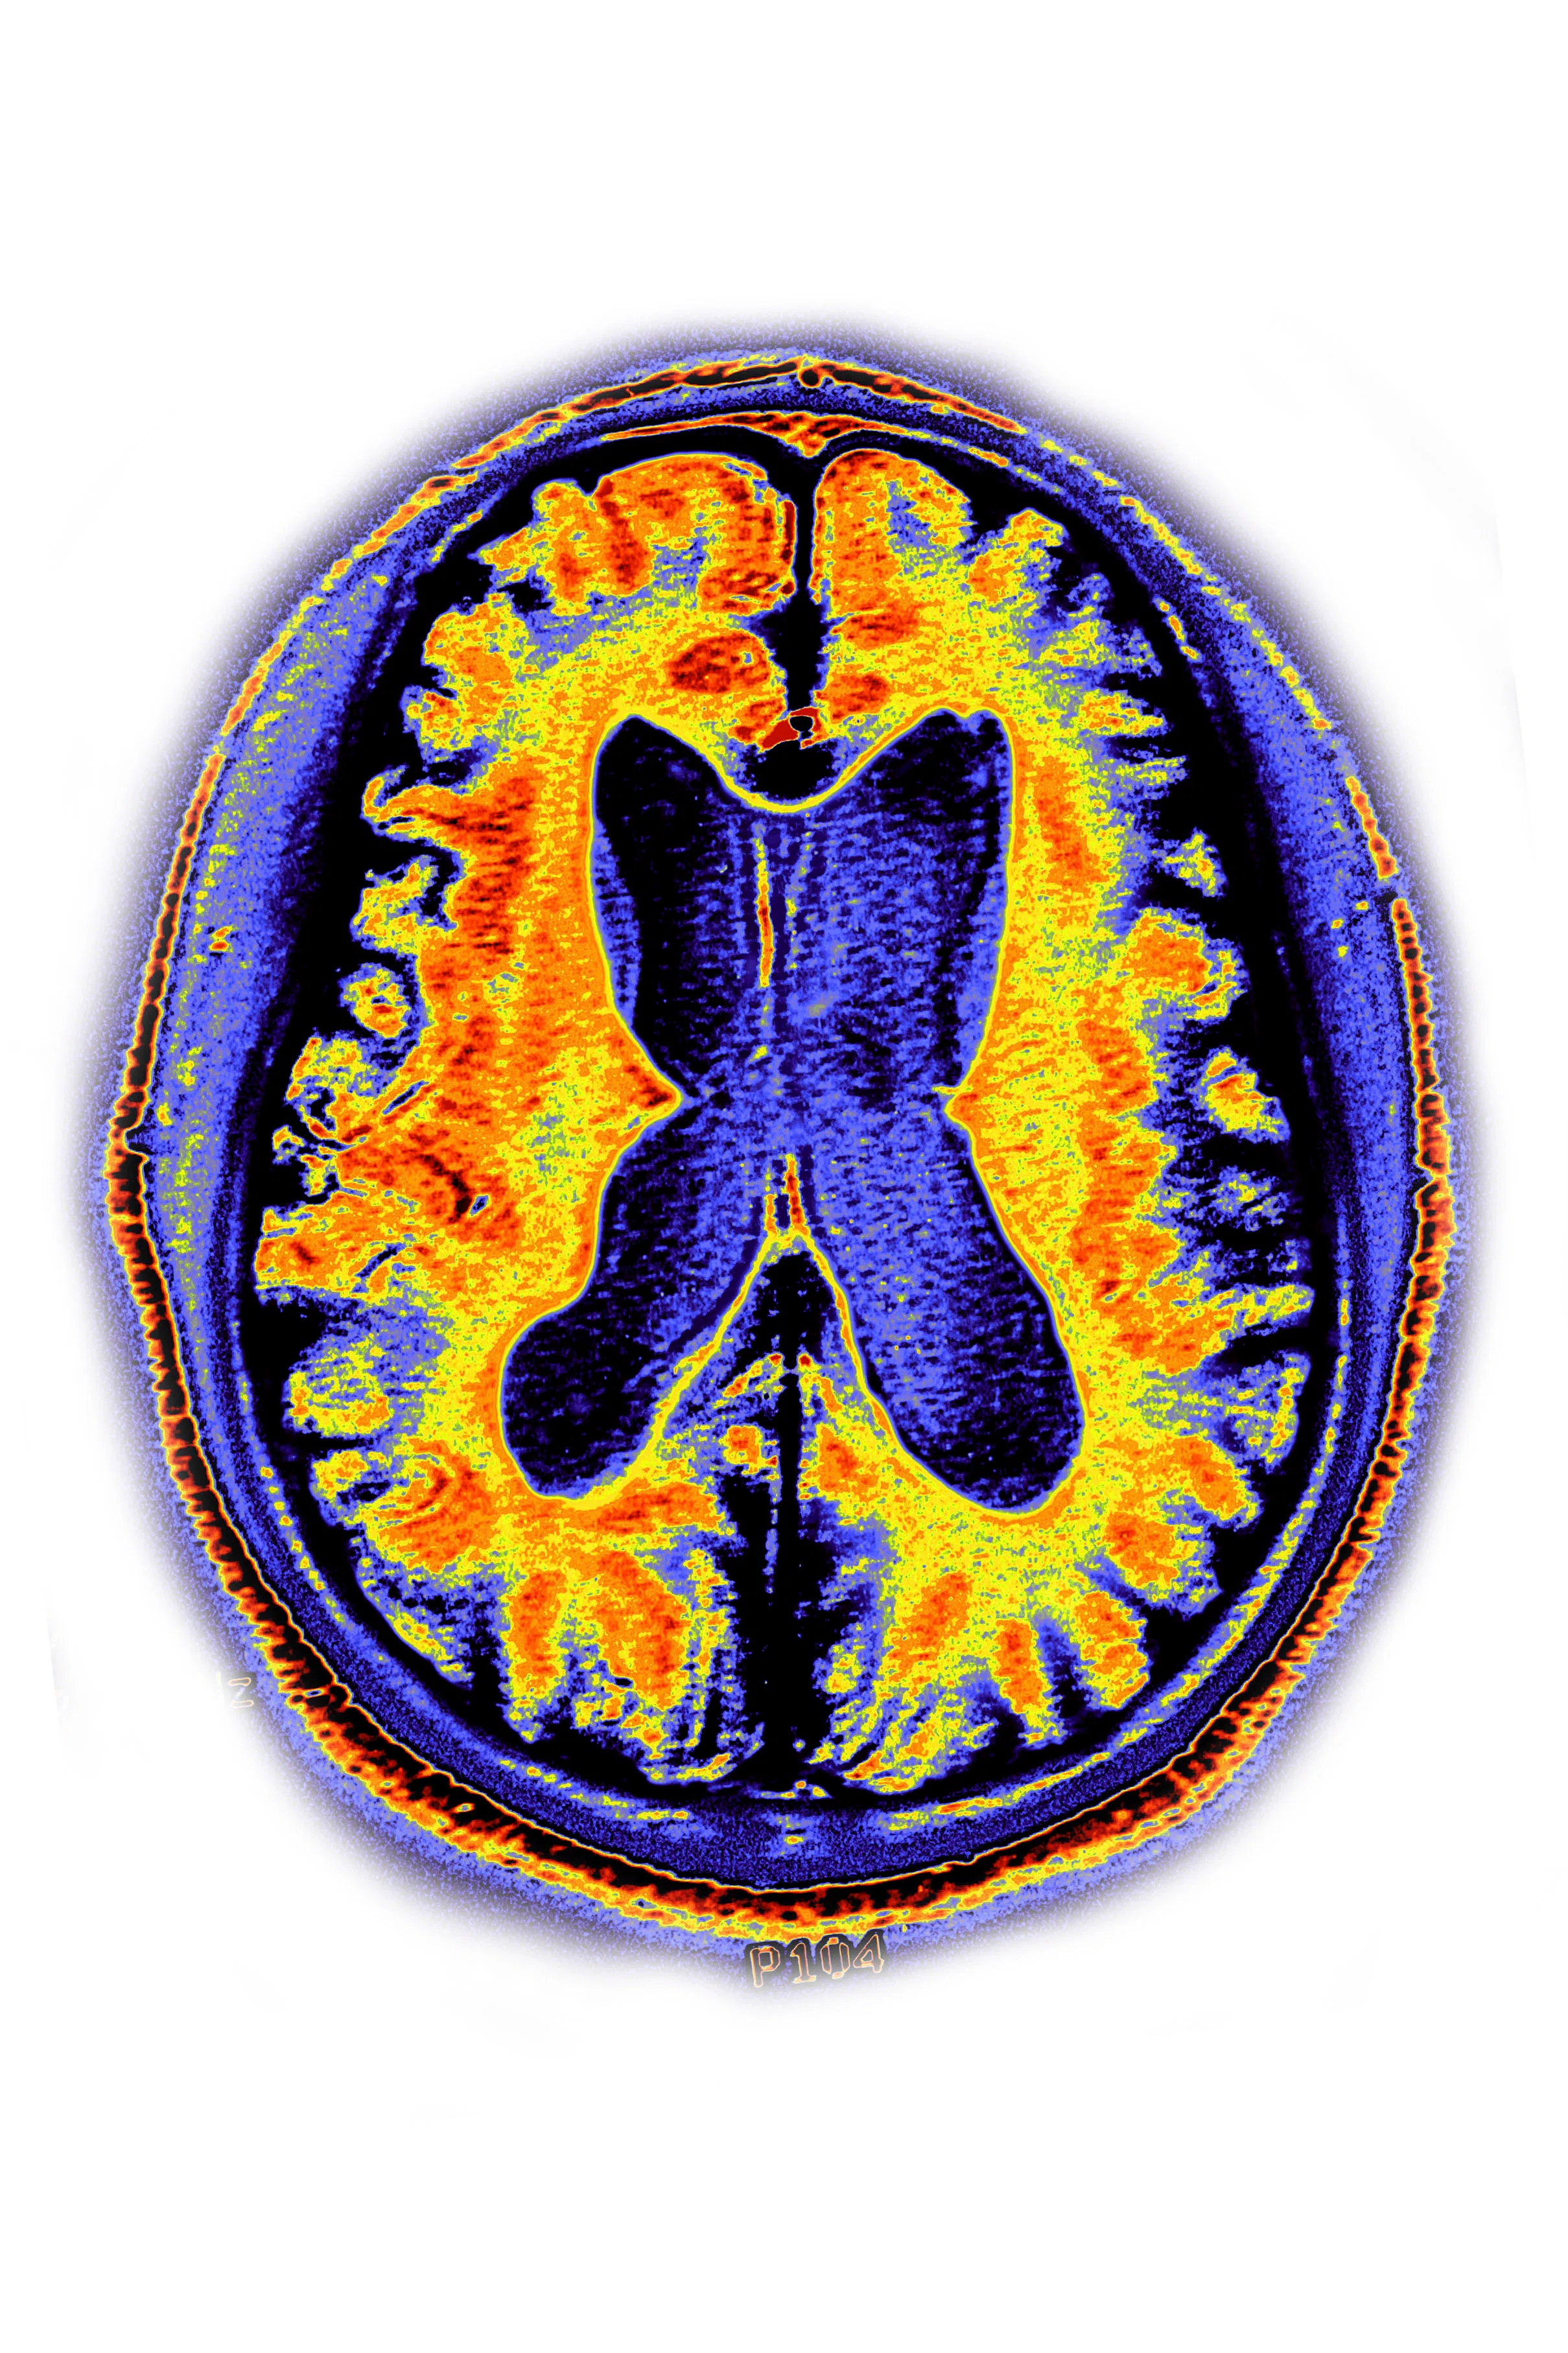

When it comes to the brain, researchers also use a more specific term called brainAGE — the difference between chronological age and age predicted on brain-imaging data.

The Frontiers in Aging Neuroscience study examined 2,000 brain scans representing 686 healthy people ranging in age from 44 to 76. Across the 12-year study period, blood pressure was measured up to four times. Observed age of the brain, or brainAGE, was assessed with the blood pressure and brain scan data.

Meanwhile, an “aging” brain can be observed on both (quite literal) microscopic and larger levels. When a brain ages, neurons and other cells shrink, and the connections between cells slow. The brain gets worse at removing the biological debris that accumulates, which eventually impairs brain function.

These microscopic changes lead to brain shrinkage, with some areas of the brain especially affected, including the hippocampus and the front of the brain. This can eventually influence a person’s ability to regulate emotions, memory, and decision-making skills.